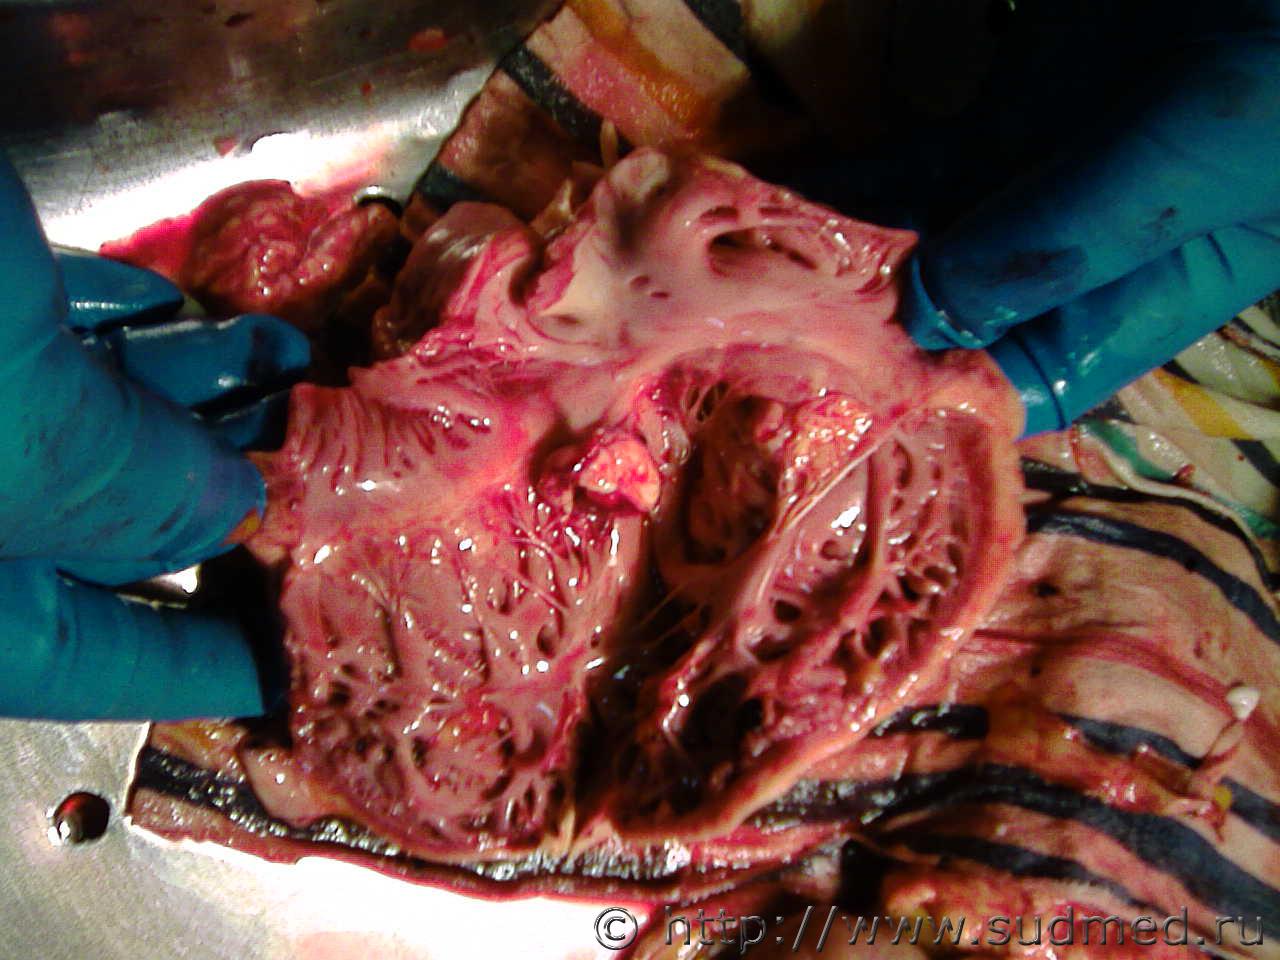

Хроническая аневризма сердца.

Судебная медицина - Прикрепленное изображение